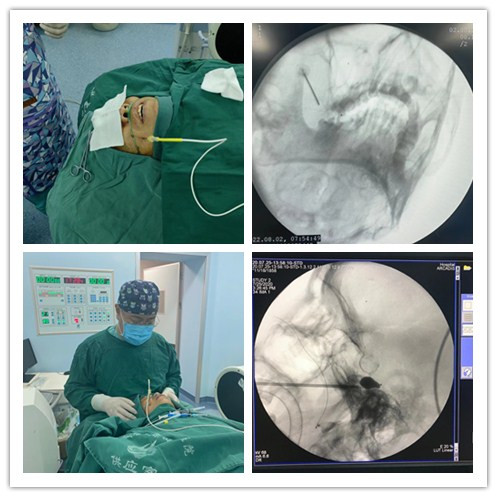

超聲引導(dǎo)下神經(jīng)阻滯、小針刀治療;周圍神經(jīng)射頻脈沖術(shù);頸腰椎間盤低溫等離子微創(chuàng)消融術(shù)、化學(xué)溶解術(shù);交感神經(jīng)節(jié)毀損術(shù);三叉神經(jīng)射頻熱凝、微球囊壓迫術(shù);脊髓電刺激植入術(shù);鞘內(nèi)泵植入術(shù)。

2、周圍神經(jīng)射頻脈沖術(shù),主要用于治療神經(jīng)病理性疼痛,如:帶狀皰疹性神經(jīng)痛、帶狀皰疹后遺神經(jīng)痛、肋間神經(jīng)痛、坐骨神經(jīng)痛等。

3、椎間盤低溫等離子微創(chuàng)消融術(shù)、化學(xué)溶解術(shù),主要用于治療各類頸腰椎間盤突出癥。

4、交感神經(jīng)節(jié)毀損術(shù),主要用于交感神經(jīng)節(jié)異常引起的下肢發(fā)涼癥狀。

5、三叉神經(jīng)射頻熱凝術(shù)、微球囊壓迫術(shù),主要用于治療原發(fā)性三叉神經(jīng)痛、三叉神經(jīng)皰疹等疾病。